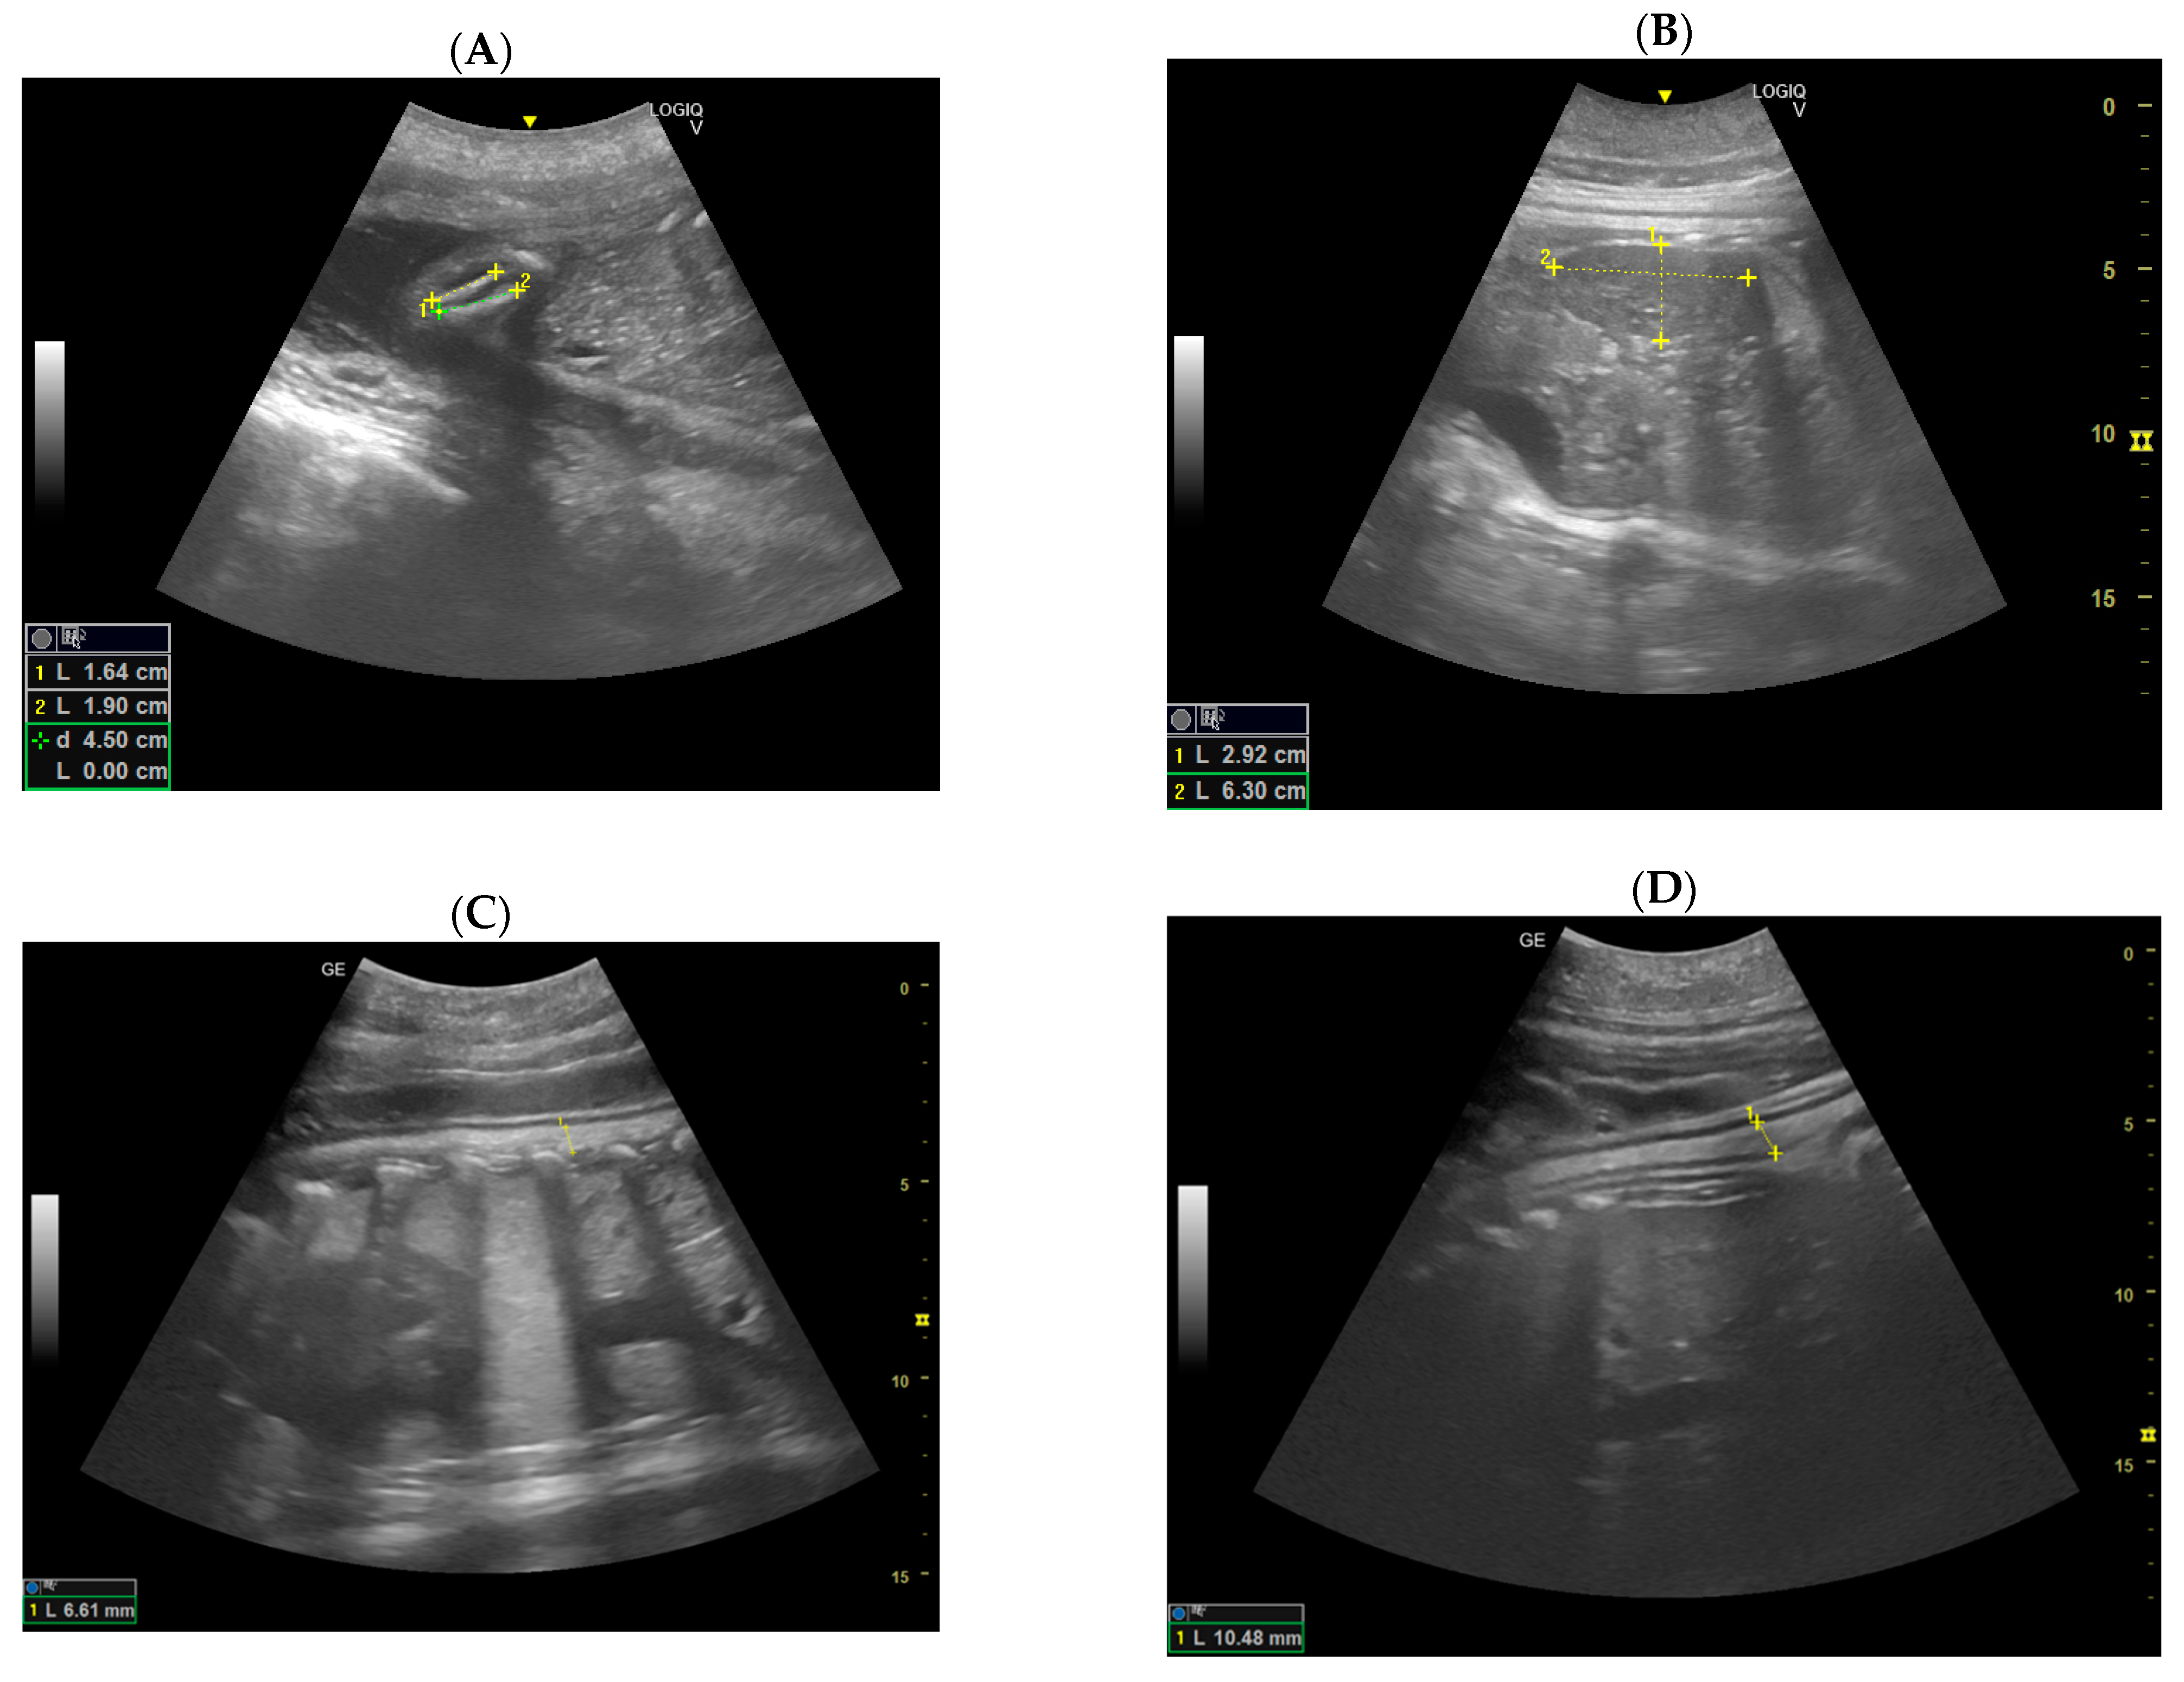

3.3. Construction of the Growth Curve of the Embryonic and Fetal Blubber Thickness

3.4. Construction of the Growth Curve of the Embryonic and Fetal Head Diameter

3.5. Construction of the Growth Curve of the Blubber Thickness